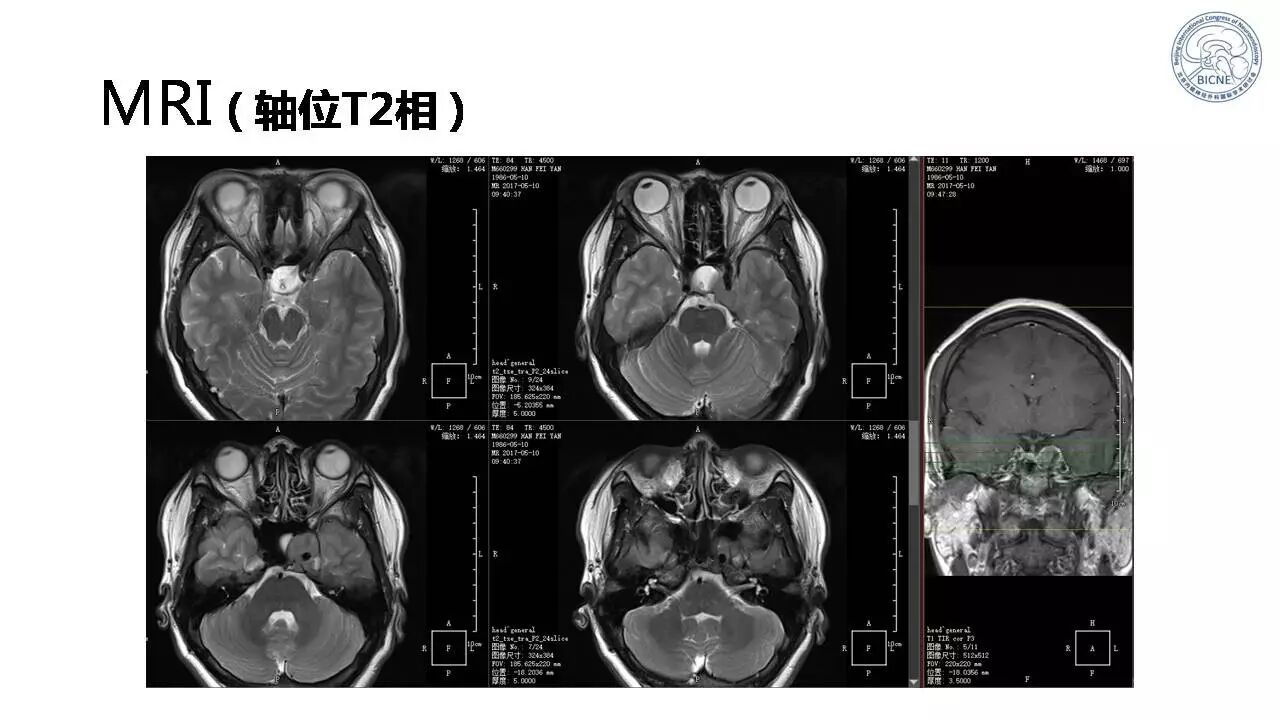

(二)张亚卓教授:侵袭海绵窦垂体腺瘤经鼻内镜治疗

![]()